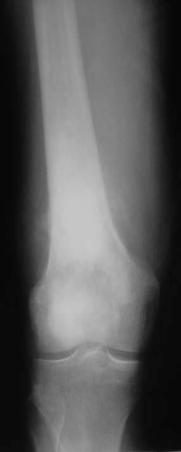

骨肉瘤:最常见的恶性骨肿瘤

临床:1、年龄:青少年(11-20岁占50%),男多于女;2、部位:以膝关节、肱骨上端多见。;;发生于干骺端。

影像学表现:1.源于骨髓腔的不规则的骨破坏和骨增生;2.骨皮质破坏,骨膜增生–葱皮样、放射状,Codman三角(袖口征)-骨膜增生被破坏形成

3.软组织肿块,其内见肿瘤骨(诊断骨肉瘤要点)。云絮状、针状、放射状、斑块状

4.不累及关节;5.病理性骨折

桡骨上段成骨型骨肉瘤:骨质增生硬化,并有骨膜反应,软组织肿块

股骨下端溶骨型骨肉瘤